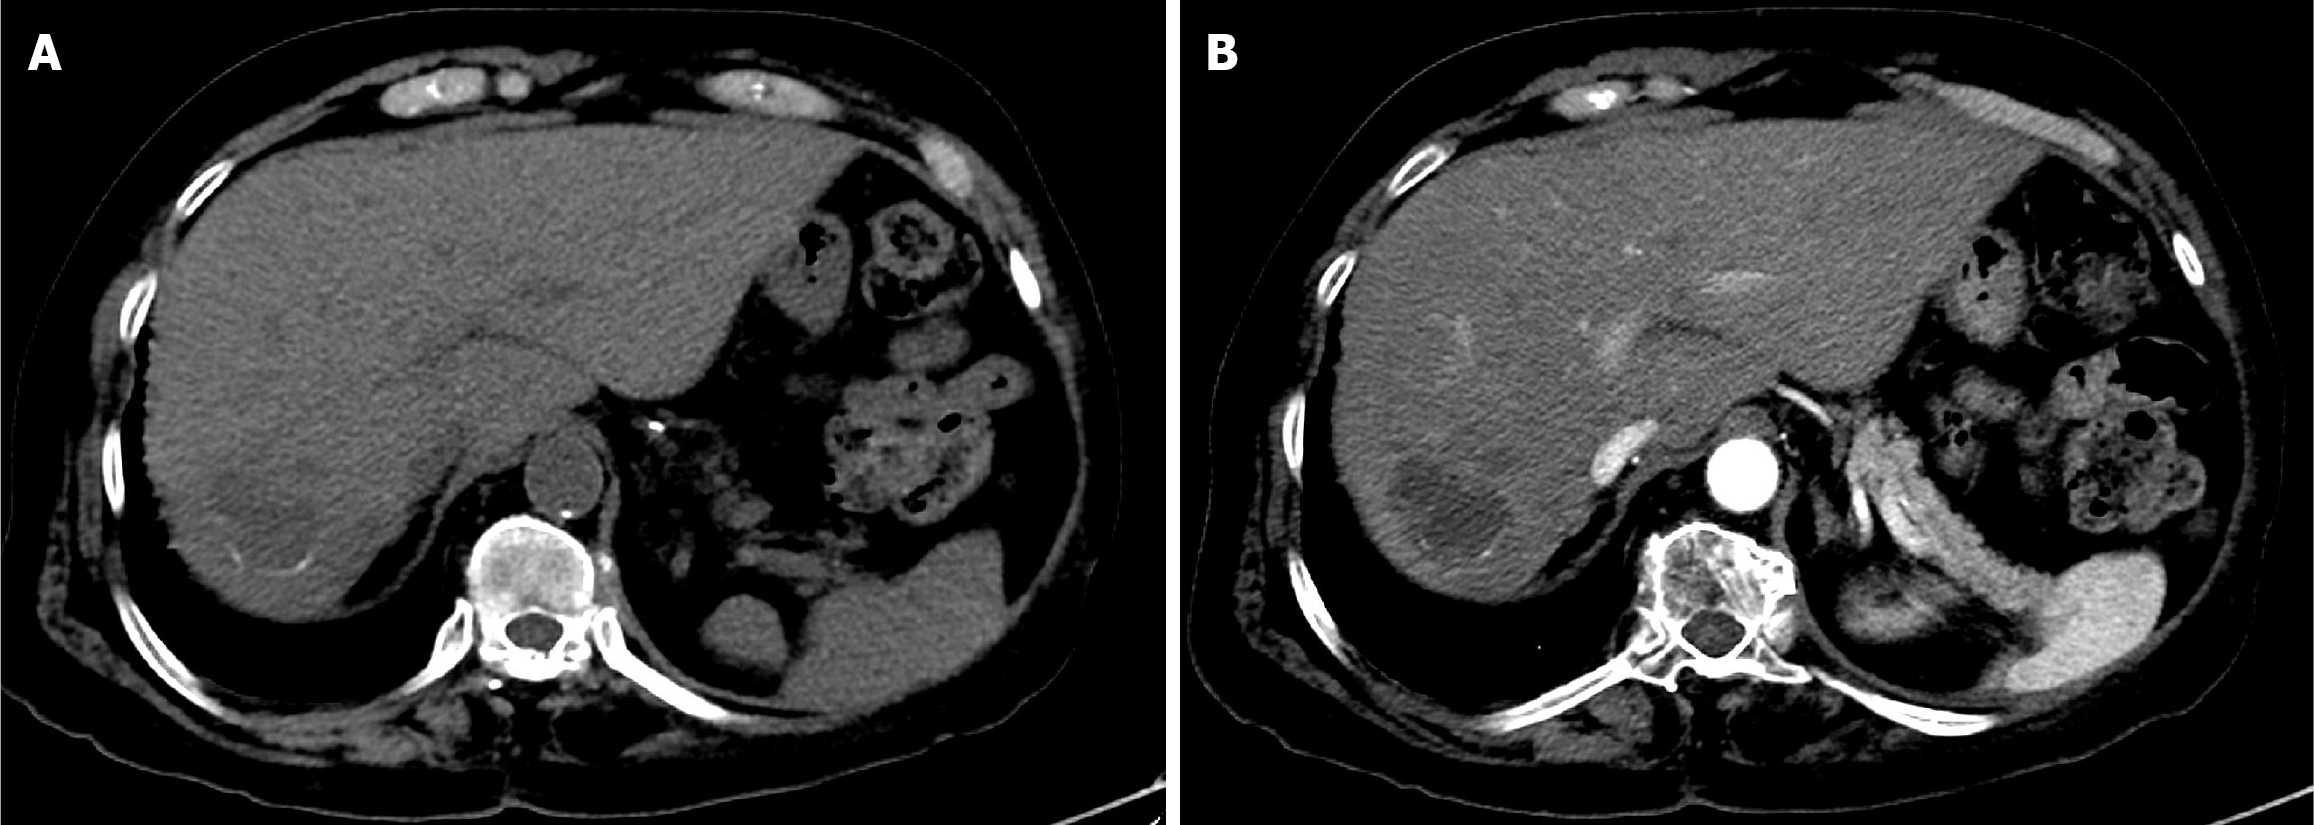

Figure 1 Baseline computed tomography of the abdomen.

A: Arterial phase computed tomography (CT) showed a large, well-defined hypervascular hepatic mass; B: Delayed phase CT demonstrated washout of the mass with an enhancing peripheral rim (tumor capsule).